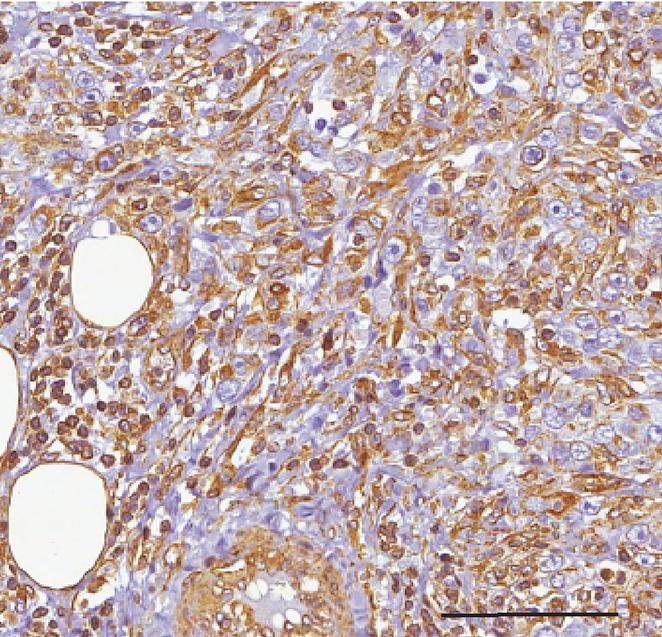

image: Tumor sample from a breast cancer patient expressing high levels of the microRNAs miR-146a and miR-146b.

In the new study, Nicassio and colleagues, including co-senior author Pier Paolo Di Fiore, a group leader at the European Institute of Oncology and professor at the University of Milan, identified two closely related microRNAs, miR-146a and miR-146b, that are present in breast cancer stem cells as well as normal mammary stem cells. Indeed, the levels of these two microRNAs tended to be highly elevated in aggressive breast cancers that have a high number of cancer stem cells and a poor prognosis.